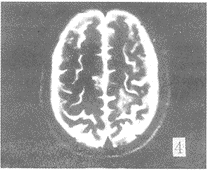

在FLAIR序列所发现81个病灶中,FSET2序列能显示的有66个,FSET2序列对病变显示率 为81.4%。FSET2序列未显示的15个病灶均位于侧脑室下、脑室旁及脑灰质区(图1,2) 。位 于脑室下的病灶,T2像未能显示。而位于基底节区,脑白质区的病灶,FLAIR及FSET2序列都 能显示。T2加权像上,所有病灶均为高信号。但在FLAIR序列,有2个病灶为低信号,1例出 血,出血灶的低信号部份T2像未能显示。另1例是T2加权像没能显示的血管畸形远端侧枝 循环(图3,4),此例为左侧颈内动脉畸形,左顶叶侧枝循环,T2像未能显示。在T2像上没能 显示而FLAIR像显示的15个病灶中,有10例为脑梗塞、脱髓鞘病变和皮层下动脉硬化性脑病 , 病灶位于脑灰质,受脑脊液影响T2像未能显示。2例为转移瘤(图5,6),肿瘤位于脑灰质,T 2像仅见水肿影。2例为脑炎、脑膜炎(图7,8),在T2像上病灶完全被脑沟中的脑脊液所掩盖 。

图1 FLAIR像示左顶叶脑梗塞灶,而FSET2像(图2)仅可见水肿影

3.2 FLAIR序列的图像特点与正常所见:FLAIR序列由于采用了较长的TE,所以为一种特 殊重T2加权象[3],组织对比类似于FSET2加权像,脑灰质信号较高,在图像上为 灰 白,脑白质为较暗的灰黑。FLAIR序列由于可以抑制脑脊液信号,重T2加权像在病理情况下 又可突出长T2成分,产生病变与背景的高对比[4]。FLAIR序列的另一特点是特定部 位的脑白质表现为高或较高信号[5],如位于脑室周围,为脑室内的脑脊液漏入室 管膜下所致。而远离脑室的白质内高信号,如半卵圆中心、枕丘放射冠、内囊后肢及顶桥束 等,可能与局部脑白质神经纤维髓鞘形成不全或髓鞘形成稀少有关。